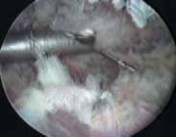

Arthroscopic Exploration and Debridement

Infraserratus Space Exploration:

- Systematic visualization of the scapular undersurface (ventral aspect) and the thoracic wall. Identify the serratus anterior muscle fibers, which will be visible on the scapular side, while the chest wall (ribs, intercostal muscles) forms the opposing surface.

- Identify the inflamed and hypertrophic bursal tissue. The bursa may be thickened, fibrotic, and contain villous hypertrophy.

Image:

Intraoperative views reveal the inflamed bursal tissue.

Magnified view of the pathology.

- Use a shaver to systematically debride the inflamed bursal tissue. Begin debriding from the medial border of the scapula and extend as far laterally as possible. Care must be taken to remove enough tissue to create a gliding space without excessively stripping muscle.